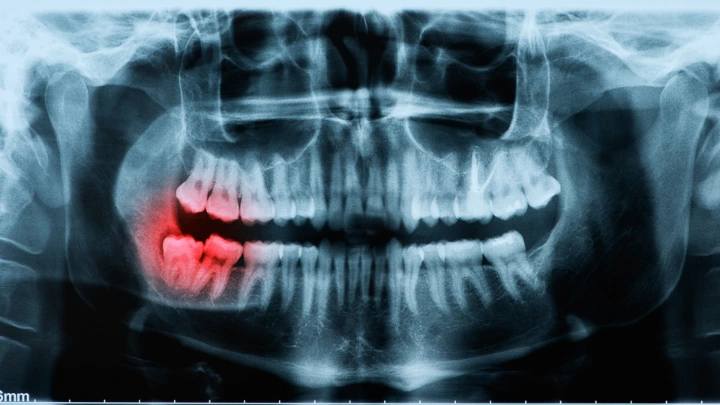

Pericoronitis adalah peradangan pada gusi di sekitar gigi bungsu yang belum tumbuh sempurna. Kondisi ini cukup sering terjadi pada usia muda, terutama mahasiswa, dan biasanya ditandai dengan nyeri, bengkak, hingga sulit membuka mulut.

Sementara itu, grafik pada halaman 6 (Figure 1) menunjukkan:

Skor mahasiswa kedokteran gigi jauh lebih tinggi

Mahasiswa kesehatan berada di tengah

Mahasiswa non-kesehatan paling rendah